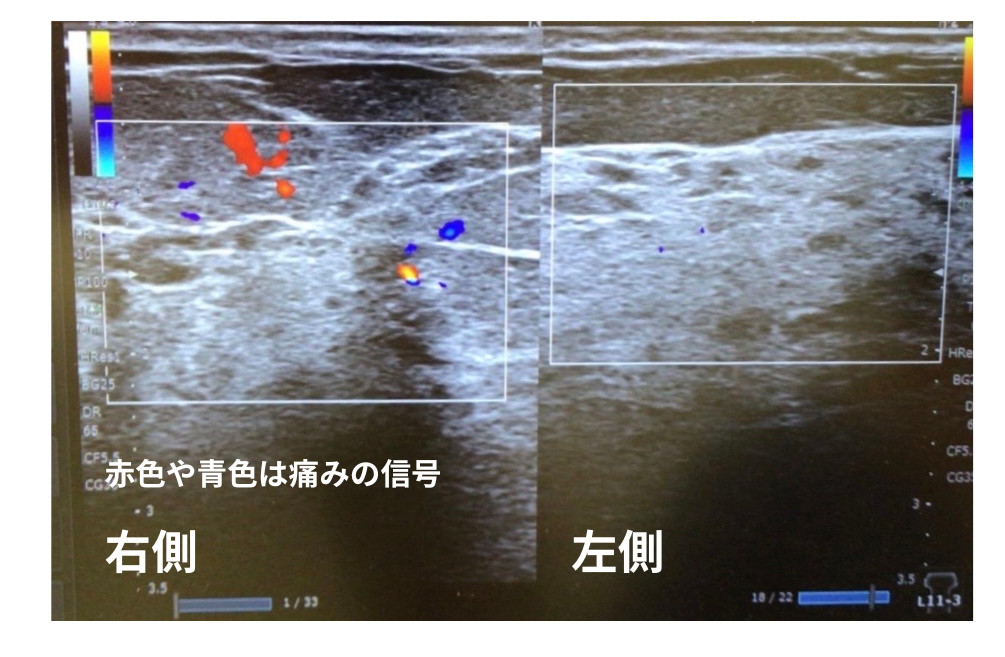

当院でエコーを使って詳しく診察したところ乳腺内にがんを疑う所見はありませんでしたが、特に右側の乳房において血管の信号が強く認められました。これは炎症が強く、本来は不要な血管「モヤモヤ血管」が増えていることを示しています。

これらの所見から、異常な血管を減らすための乳房に対する動注治療を提案しました。

脇の下を走る「腋窩動脈(えきかどうみゃく)」から、非常に細い針を用いて炎症を抑える薬剤を投与します。(下記写真参照)薬は腋窩動脈から乳房へ向かう血管に流れ、痛みの原因となっているモヤモヤ血管に直接アプローチして治療する方法です。